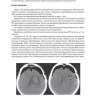

Анализ исходов у больных с интраоперационным тромбозом артерий